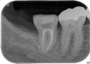

当時の歯の移植は、移植歯を抜歯したら、歯の根の表面の徹底的な清掃(掻爬)と、根管治療を口腔外で行いその歯を移植していました。しかし、それでは移植歯は移植された所の歯槽骨(もともとの歯を支える骨)とどんなに上手くいっても骨性癒着を起こします。この癒着した歯の根は時間と共に周囲の骨組織に吸収され、やがて歯の根はあとかたも無くレントゲンから消え去り、まるで乳歯が抜けるように根の無くなった歯が抜けていきます。これが5年もてば成功といわれた所以です。

現在は、ドナーとなる歯の抜歯前に移植される側の処置を終了し、ドナーの歯を抜歯するとほぼ同時に、当院では3秒以内に受容側の中にドナーの歯を入れます。これはとても速いスピードであるといえ、このスピードで確実に行う為に、いろいろな研究を行い、CTスキャンのデータを応用した現在の移植のシステムを構築致しました。

このようにして移植された歯は、歯の根の表面にある歯根膜と言う組織がほぼ完全に保存され、生着(生きた状態で移植されて機能する事)する事によって、将来矯正治療で歯を移動する事もできますし、被せもの等を行えば全く移植歯である事は気が付かれないレベルで仕上がります。